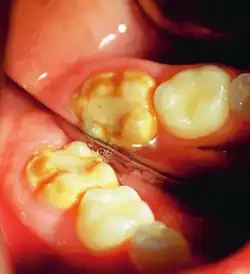

Enamel hypocalcification is characterized by visible defects in the enamel, often manifesting as white spot lesions or brown discolorations.[35] In cases such as dental fluorosis, this may include mottled patterns on the enamel surface which vary in appearance and extent based on the severity of the condition.[36] In advanced cases, the mottled appearance of the enamel can expose the underlying dentin, creating an uneven and sometimes porous surface. Though the matrix of the enamel initially forms to a typical thickness, the mineralization or calcification process is incomplete or deficient, leading to softer and structurally compromised enamel.[35]

This compromised enamel is more susceptible to staining due to its rougher surface texture and increased permeability, which allows pigments and external elements to penetrate more easily. The weakened enamel may begin to wear away, especially on the occlusal surfaces of the molars, where mechanical forces are most intense. In some individuals affected by severe enamel hypocalcification, the structural deficiencies also contribute to anterior open bite where the upper and lower front teeth do not meet when biting down. This malocclusion can further complicate both functional and aesthetic aspects of the dentition.[37]

It occurs as a result of severe hypomineralization of the enamel as the enamel appears intact in the initial stages but gradually chips and fractures after the tooth erupts due to the weakened mineral content hence, leading to the formation of rough surfaces and cavities which makes the tooth highly vulnerable to undergo wear, decay and sensitivity.[26] Notably, the post-eruptive breakdown is linked to severe forms of hypomineralization like molar incisor hypomineralization (MIH).[27]